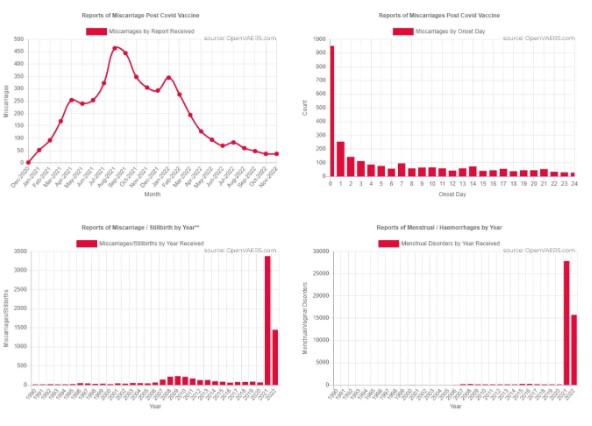

No hay nada que ver aquí. No preste atención al aumento del 4,070% en abortos espontáneos y mortinatos, según lo informado por el Sistema de Notificación de Eventos Adversos a las Vacunas (VAERS). El sistema VAERS es el método del gobierno federal para controlar las lesiones causadas por las vacunas mediante informes en tiempo real.

Pero lo que no está recibiendo mucha atención es el increíble aumento de abortos espontáneos y mortinatos. Los siguientes gráficos muestran los dramáticos aumentos según OpenVAERS:

Los abortos espontáneos parecieron repuntar en 2008 en torno a la vacuna contra el VPH. Esa cifra superó ligeramente los 160 casos (165). En 2021 y 2022, hemos visto 3.379 y 1.445, respectivamente, relacionados con las vacunas COVID.

Cabe mencionar que un estudio de Harvard estima que solo se notifica un pequeño porcentaje de las lesiones reales del VAERS. El proceso es engorroso para médicos y enfermeras y hay denunciantes que han afirmado que se les “desalienta” a escribir informes VAERS, a falta de un mejor término. El número real es probablemente mucho mayor.